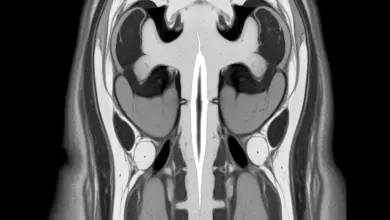

- Ressonância magnética: avalia medula espinhal, raízes nervosas e eventuais anomalias associadas, como diastematomielia ou siringomielia.